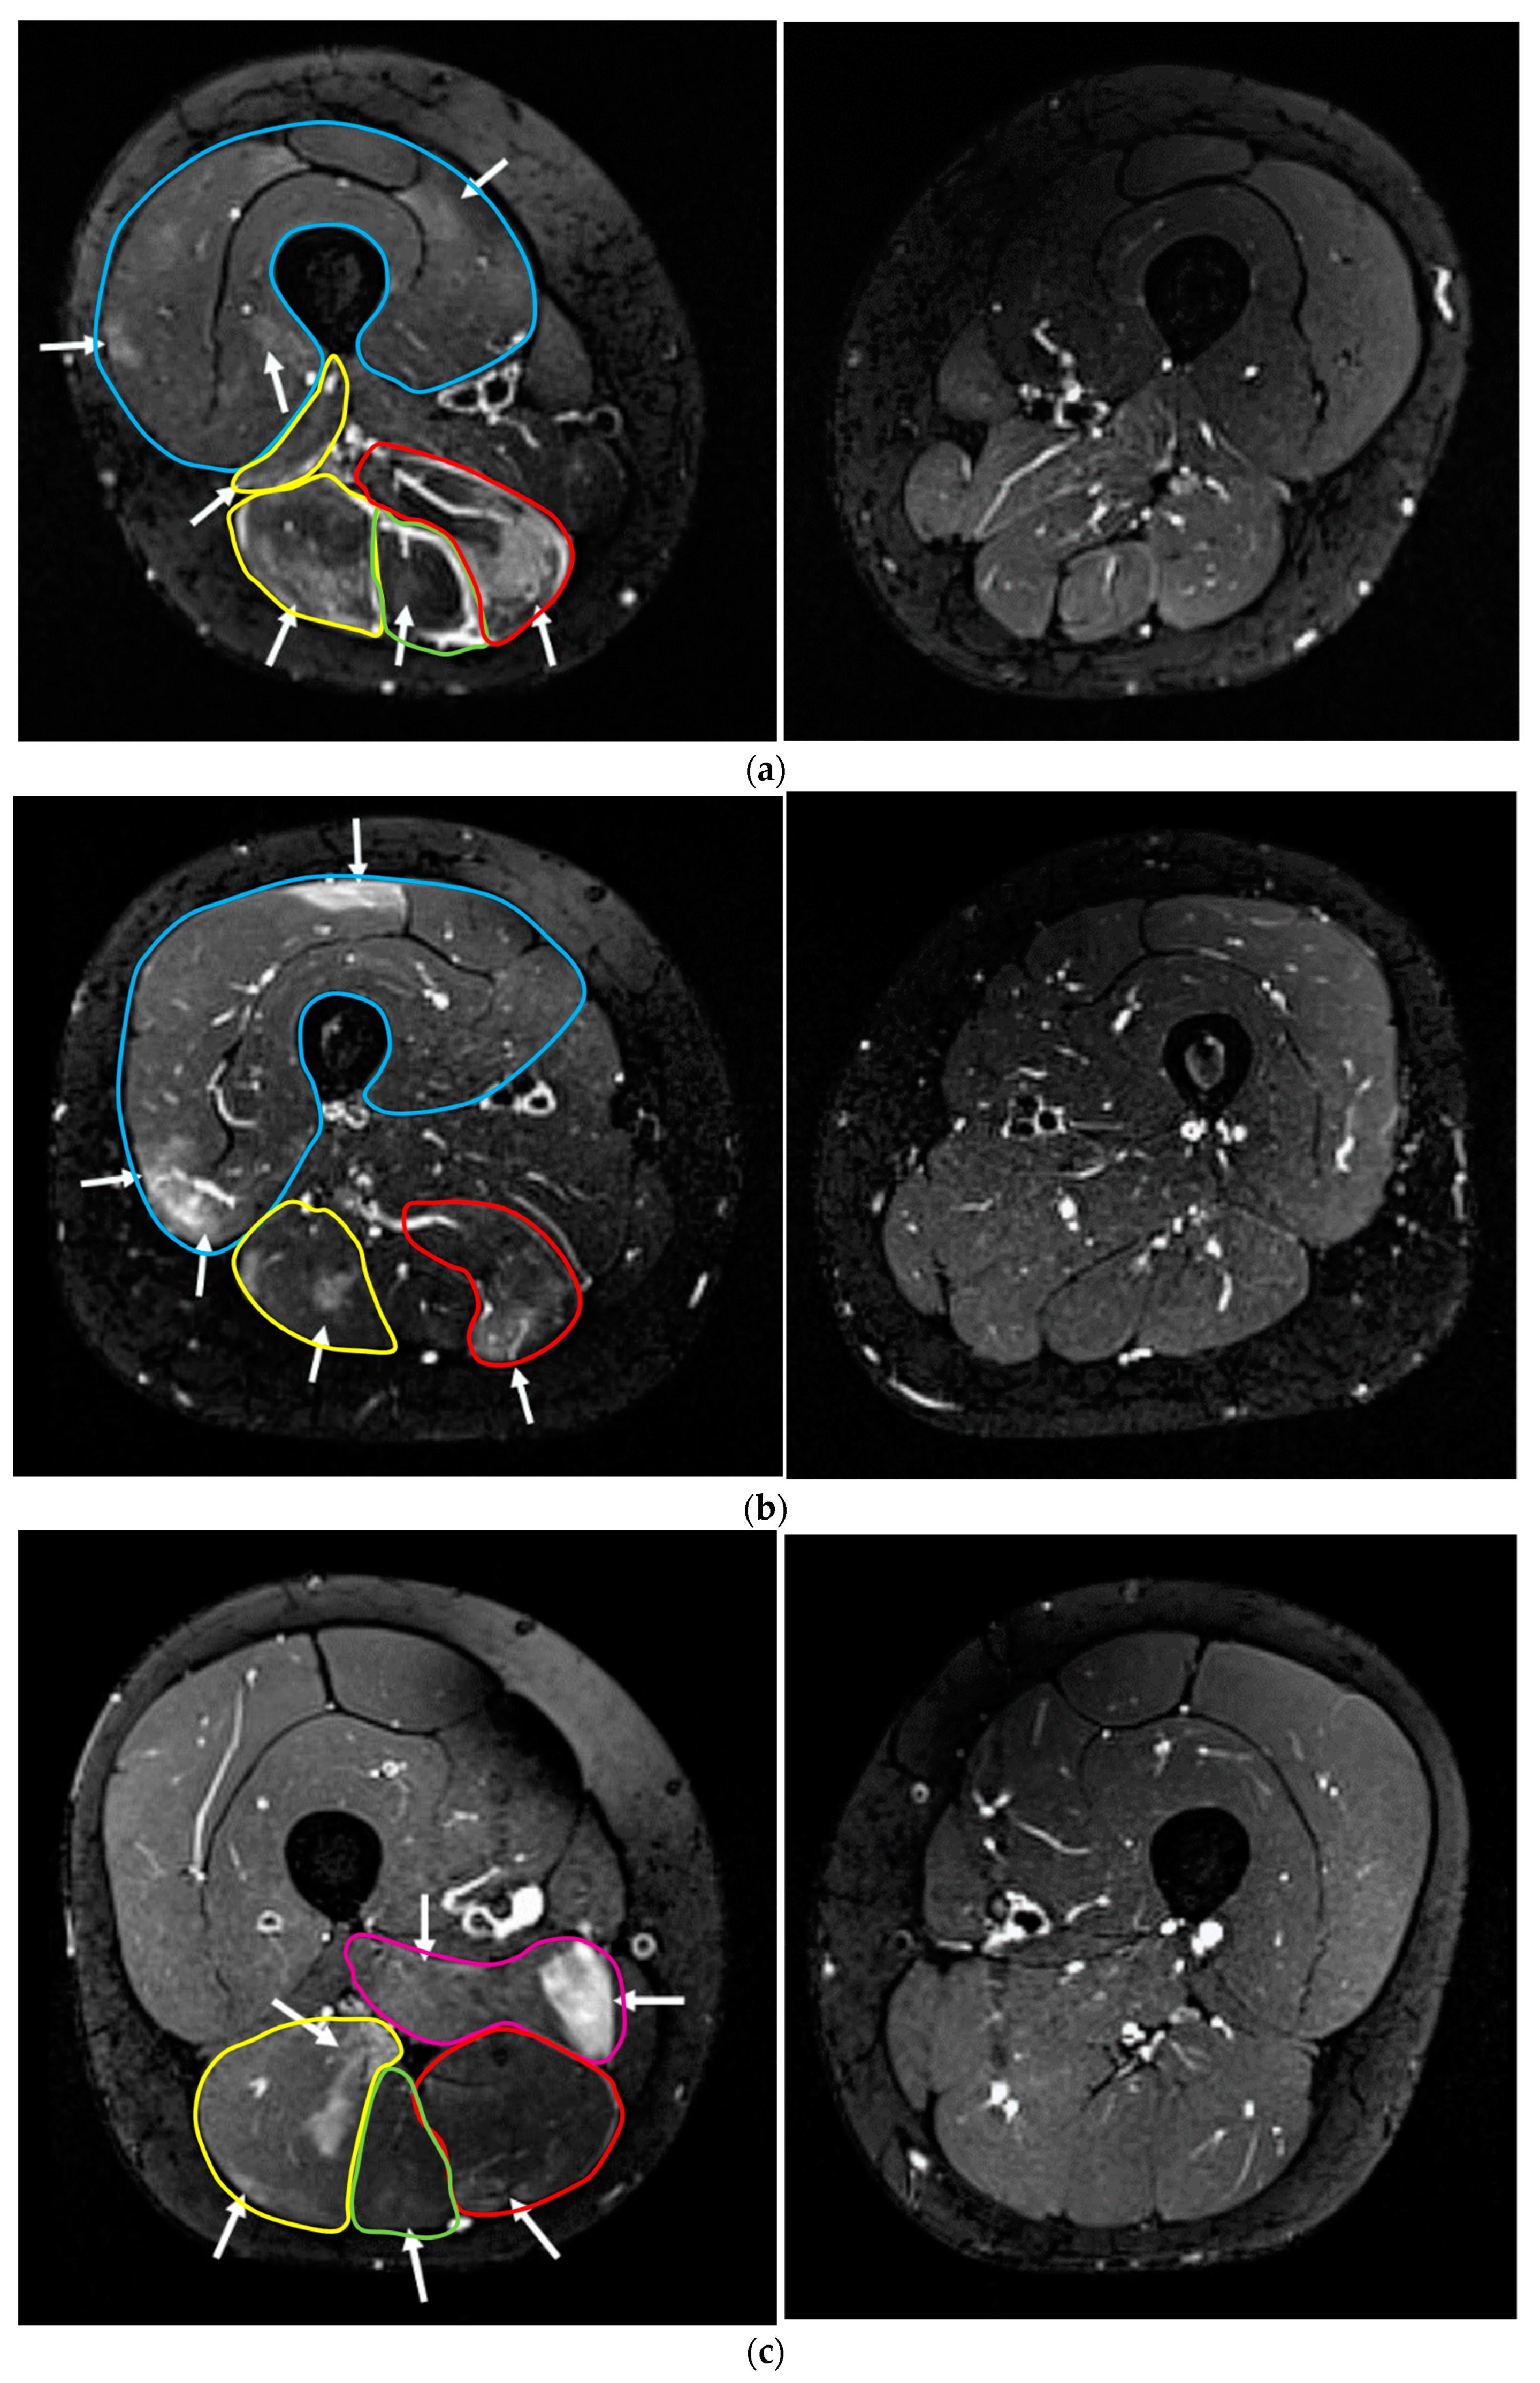

3.3.2. Lower Leg

| Compartment of the Edema | Participants with Edema (Total: n = 8) | Maximum Depth of the Edema from Skin (mm) MV ± SD, (Range) | Intramuscular Edema Volume Grading MV (Range) |

|---|---|---|---|

| m. gastrocnemius medialis | 8 | 24 ± 5; (18–33) | 1 (1) |

| m. gastrocnemius lateralis | 7 | 26 ± 4; (21–31) | 1.3 (1–2) |

| m. soleus | 6 | 35 ± 14; (19–51) | 1.2 (1–2) |

| m. peroneus longus | 4 | 31 ± 4; (25–35) | 1 (1) |

| m. extensor digitorum | 1 | 25 | 1 (1) |

| m. tibialis posterior | 2 | 42; 56 | 1 (1) |